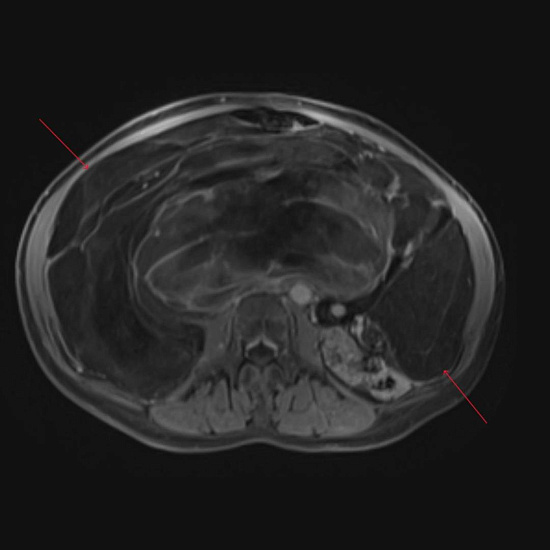

С целью оценки образования, а также уточнения расположения и взаимоотношения с органами брюшной полости проведено МРТ органов брюшной полости с внутривенным контрастированием.

При МРТ было выявлено жиросодержащее внеорганное объемное образование больших размеров с множественными неравномерными накапливающими контрастный препарат перегородками, занимающее большую часть брюшной полости с признаками смещения прилежащих внутренних органов.

Учитывая особенности структуры образования, распространенность и расположение, находка расценена как липосаркома (злокачественная опухоль жировой ткани).